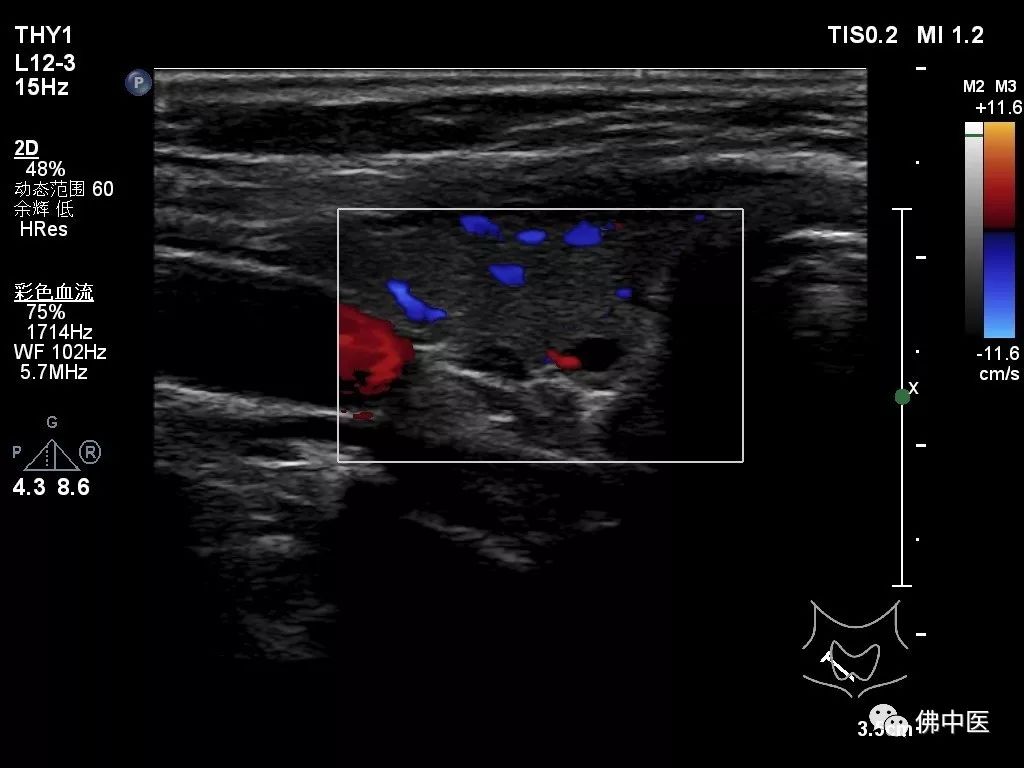

基于此种临床特点,劳永锵教授组织主管医生胡永波、潘海文请我院普通外科为两名患者进行会诊,普通外科霍景山博士详细诊查了两名患者,考虑他们为:“甲状旁腺功能亢进并甲状旁腺瘤”,建议转普通外科行手术治疗。

病例二(甲状腺彩超)

其后,两名患者均接受了手术治疗,术后病理均提示“甲状旁腺腺瘤”。术前诊断得到进一步印证,两位患者目前康复良好并已出院。